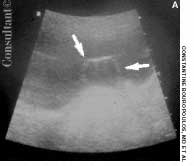

Levofloxacin, 500 mg/d, had been prescribed for a 74-year-old woman who had a urinary tract infection. The patient had type 2 diabetes and hypertension. She was allergic to sulfa drugs. Two hours after taking the first oral dose of the antibiotic, painful blisters developed on the lower lip and soft palate.